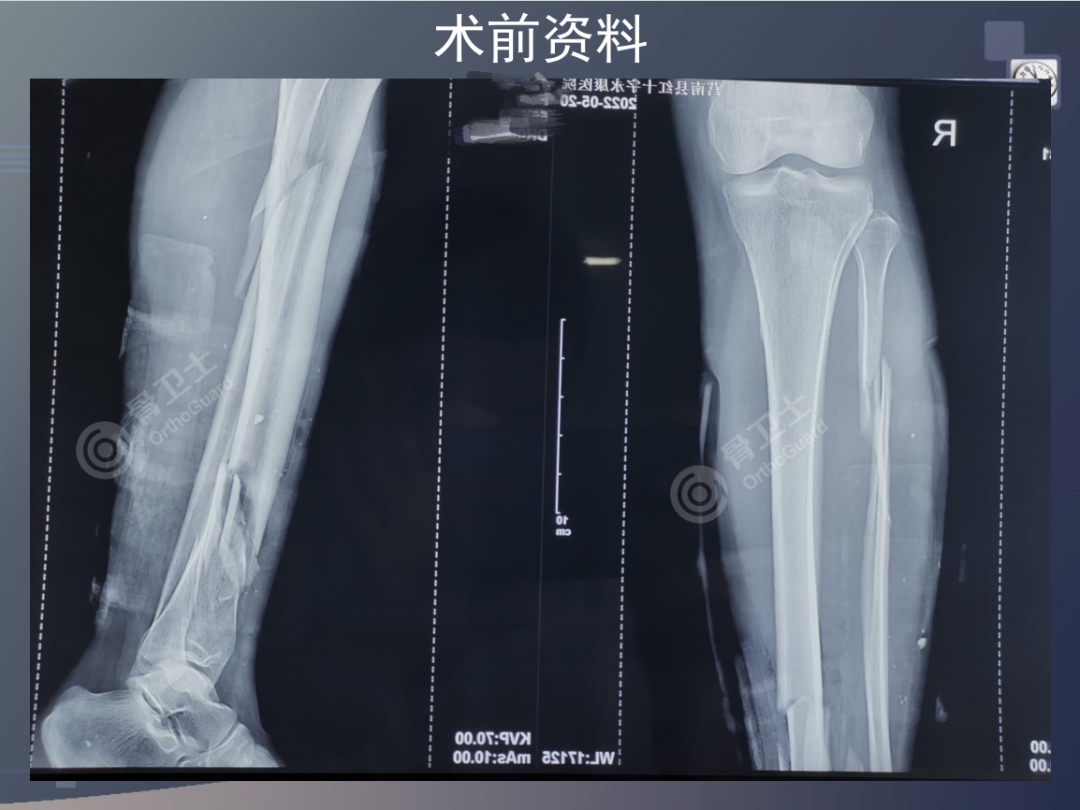

基本情况:女,56岁,因右小腿外伤后疼痛流血2小时入院。

查体:右侧小腿肿胀明显,右小腿中下端内侧见一直径约0.5cm皮肤伤口,流血,皮肤边缘整齐,污染轻,无张力性水泡,小腿中下1/3处及小腿上端外侧压痛明显,扪及骨擦感及异常活动,踝关节因疼痛活动受限,被动活动疼痛明显,无被动牵拉疼,足背动脉搏动正常,足趾感觉、活动正常。肢体远端血运未见异常。

诊断:右胫腓骨开放性骨折。

▲患者术前影像